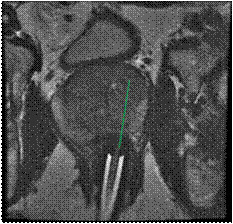

Here is an example of 61 year old man who had rising PSA and negative transrectal prostate biopsies. The patient had five prior transrectal ultrasound biopsies with estimated 51 cores obtained over multiple years:

Figure 4: Following the diagnostic MRI he underwent a MRI Guided prostate biopsy where only 2 cores were obtained through the left sided suspicious region in the prostate gland.

MR guided prostate biopsy-2cores revealed an intermediate risk prostate cancer with Gleason Grade 7 (4+3)